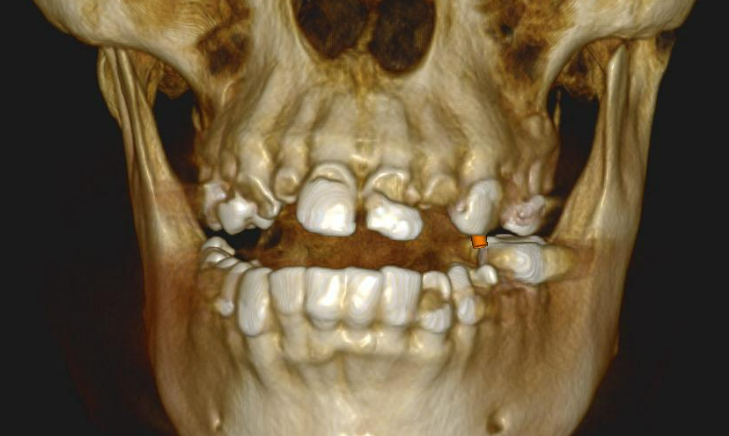

The implants were placed immediately following tooth extraction. They were positioned subcrestally — 2–3 mm below the bone crest — to allow for anticipated bone remodeling. A total of eight implants were placed in the maxilla and four in the mandible.

Placing the implants into the fresh extraction sockets allowed for optimal positioning for the future prosthetic restoration. The extractions were performed using the root shield technique, which is aimed at maintaining the thickness and height of the buccal and palatal bone walls. This technique, traditionally used for “conservation” even in case of delayed implantation, helps to minimize resorption and preserve the natural morphology of the alveolar ridge.

Implant Placement Diagram

| Tooth Position (FDI) | Implant System | Size (Ø x L) and Purpose |

|---|---|---|

| #11, #12 | XGATE Dental | 3.75 x 15.2 mm (Anterior Maxilla) |

| #34 | XGATE Dental | 4.2 x 10 mm (Mandibular Premolar) |

| #16, #26 | DSI Implants | 5.0 x 10 mm (Molar Region) |

| #13, #14, #23 | DSI Implants | 3.75 x 15.2 mm (Anterior/Premolar Region) |

| #36, #45, #47 | DSI Implants | 4.2 x 10 mm or 5.0 x 10 mm (Mandibular Region) |

| Total: 12 Implants | 3 XGATE, 9 DSI (Correction: 8 DSI) | Optimal Prosthetic Support |

Implant dimensions were selected based on the patient’s anatomy and the anticipated functional load in each area:

- Molar region: 5.0 x 10 mm

- Anterior region: 3.75 x 15.2 mm

- Mandibular premolar region: 4.2 x 10 mm